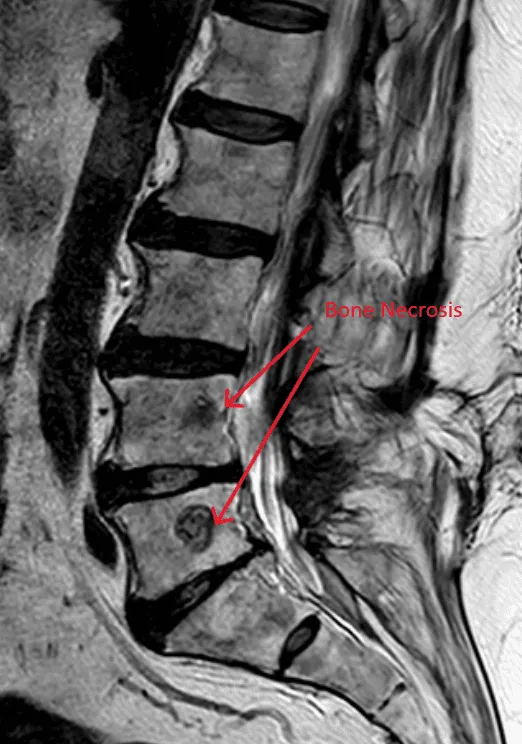

MRI image showing spinal bone destruction, highlighted by red arrows and text.

Destroys Normal Bone & Bone Marrow

MRI of the lower spine highlighting bone necrosis with red arrows.

Bone Necrosis (Bone Death)